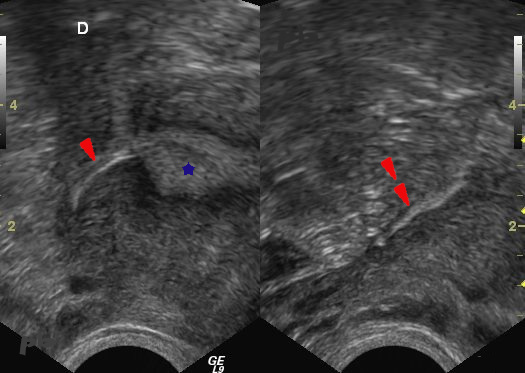

Transvaginal ultrasound.

The right implant is first visualized in the interstitial segment of the tube (►), then in the proximal portion of the isthmic segment (►►).

Endometrium and uterine cavity (★).